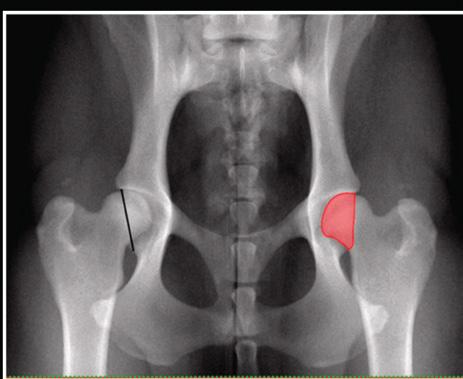

Figure 1

Ventrodorsal pelvic radiograph of normal coxofemoral joints (left) indicating the cranio-caudal distance of the dorsal acetabular rim (CrCdAR), the shortest distance (black line) between the craniolateral edge and the caudolateral edge of the acetabulum and (right) surface coverage of femoral head (CFH, red area). Photo credit PMC